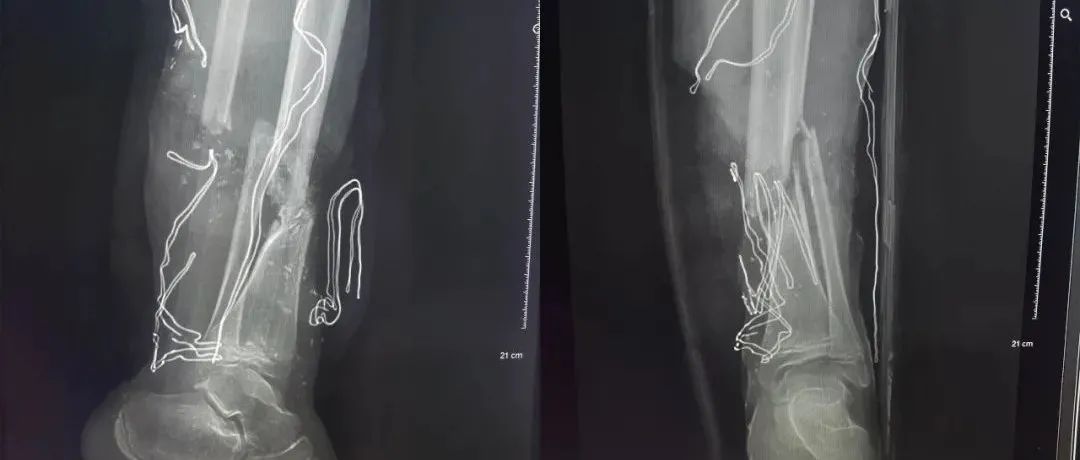

2021 最难忘病例 —— 12 岁儿童下肢离断保肢

不说废话,直接上图 !!!患者:男,12 岁。搅拌机砸伤左小腿致离断 2 小时,出血疼痛,活动受限,为求保肢,来诊。入院时 X 线:胫腓骨粉碎性骨折,创面内可见颗粒状污物。消毒、清创后外观消毒后外观清创后外观上下滚动查看更多清理后探查病情1、左小腿不全离断,仅后外侧 6 宽约 5 公分组织相连,肢体无血运。2、胫腓骨开放性骨折,骨缺损。3、胫前动脉长段缺损,约 10 公分、胫后动脉栓塞,腓动脉损伤,大隐静脉栓塞,小隐静脉断裂。...